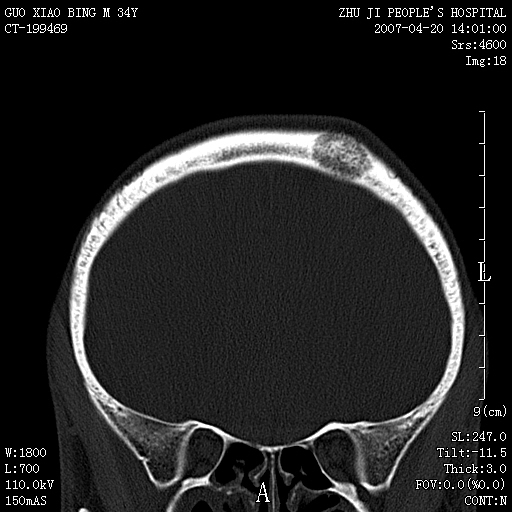

以下是引用qiuleiyu在2007-4-27 16:41:00的发言:[br]ct左侧额顶部囊性膨胀性骨质破坏,边缘有轻度硬化,其内示多发点条状高密度。[br]mri;t1低信号,t2明显高信号。界清。增强后明显强化。[br]综合考虑;颅内血管瘤。上传该病例,目的在于加深印象,共同学习。[br]骨血管瘤好发于颅骨及椎体。为良性肿瘤。组织学上分海锦型及毛细血管型。前者多见。[br]颅血管瘤典型影像学表现;[br]1,平片;类圆形骨质破坏,边缘硬化,内示中央向周边年轮状辐射(残存增粗骨小梁)。[br]2,ct;颅内板障内膨胀骨质破坏,边缘硬化,内示密集点状及放射状骨针影。[br]3,mr;t1、t2高信号。该病例t1不高可能与血流较丰富有关。边缘低信号。增强明显强化。[br]鉴别;[br]1,脑膜瘤;主要累及内板,与血管瘤发生于板障不同。颅板骨质增生硬化,与颅内垂直放射状骨针。与血管瘤日光放射状不同。增强可见脑膜尾征。[br]2,嗜酸性肉芽肿;起自板障溶骨性骨质破坏。内无点状及放射状高密度影。边缘硬化不明显。局部可有骨膜反应。[br]3,转移性肿瘤;溶骨破坏边缘模糊,无硬化边。发展迅速。有原发肿瘤史。可多发。可出现软组织块。[br]4,单发骨髓瘤;发病年龄较大,临床可能全身骨质疏松,骨痛。免疫球蛋白增高。部分病例本周氏蛋白可增高。可有边缘硬化,然内无点状高密度影。[br]